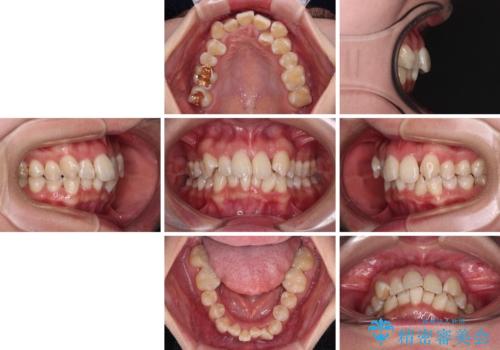

【モニター】前歯のデコボコをワイヤーの抜歯矯正で綺麗に整える

- 前歯1本が後ろ側に隠れてしまうほどのデコボコを気にして来院された患者様です。

前歯のデコボコが顕著なのはもちろんですが、左右ともに奥歯の咬み合わせに問題があり、上顎臼歯が前方位にある状態でした。

上顎は左右の第一小臼歯2本を、下顎は左右第二小臼歯2本を抜歯することで、奥歯の咬み合わせを改善しながら、デコボコを解消していくこととしました。

奥歯の咬み合わせ改善にはどうしても長期間を要します。

3年強とお伝えしておりましたが、予想通り3年3ヶ月で治療を終えることができました。